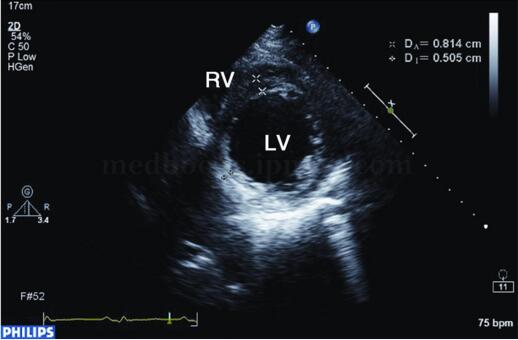

图2‐1‐179 左室短轴切面显示下后壁心肌明显变薄,回声增强

二维超声表现为左室显著扩大,几何形变,可呈球形扩张(见图2‐1‐179),左室心肌节段变薄,回声明显增强,运动明显减弱或消失,室壁增厚率消失,并伴有左室壁普遍运动减弱和不协调,左室泵血功能明显减低(见图2‐1‐180),二尖瓣开放幅度减低。左室腔内血流速度常较缓慢,有时可见附壁血栓形成。

扩张型心肌病 与缺血性心肌病同样表现为左心增大,左室呈球形扩张,左室收缩、舒张功能减低。不同点有:左室心肌无节段性变薄和回声增强,向心运动普遍减低。临床无冠心病病史,心电图和冠状动脉造影可帮助鉴别。